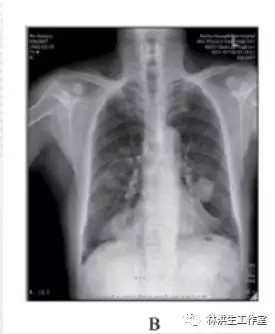

【现病史】2013年8月到中国人民解放军309医院就诊,查肺部CR片: 左肺上叶舌段占位( 3.1×3.8 cm2) ,右肺下叶占位( 1.3×2.4 cm2)( 见图 2) ,考虑恶性占位。行 CT 引导下肺穿刺活检病理( 病理号: 186488) :( 肺) 穿刺组织示弥漫增生的淋巴组织,细胞较为一致,结合免疫组化病变符合肺黏膜相关边缘区 B 细胞淋巴瘤( 见图1) 。患者因肿瘤较大,且伴顽固瘙痒,建议行化疗治疗,但患者因惧怕化疗不良反应而拒绝化疗。遂求诊于林洪生教授,寻求中药治疗。刻下症: 患者瘙痒剧烈,口服氯雷他啶、泼尼松等药抗过、外用倍氯米松止痒均无明显缓解,全身散在淡红色小丘疹,无疼痛,无咳嗽,无胸闷胸痛,因瘙痒无法入睡,二便正常,胃纳可。

A: 2013 年 8 月 23 日发病时,胸部 CR 片显示双侧肺肿物;

B:2014 年 7 月 26 日复查,经治疗显示双肺肿物缩小;